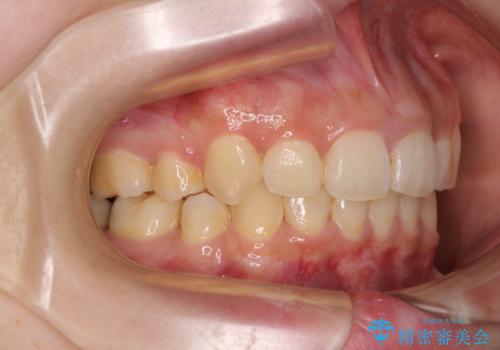

下顎前歯が隠れて突出した口元 ワイヤー装置での抜歯矯正

- 前歯のデコボコと口元の突出感を気にして来院された患者様です。

下顎骨の左右差や、上顎骨の前方位などが認められたため、上下左右の第1小臼歯4本を抜歯し、ワイヤー装置にて矯正治療を行うこととしました。

骨格的な左右差がありましたが、何とか当初予定していた期間で、左右対称の咬み合わせに仕上げることができました。